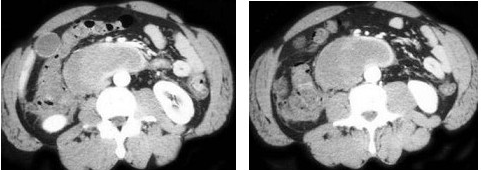

7、单项选择题

男,65岁,腋下触及肿大包块,全身浅表淋巴结肿大,结合所示图像,最可能的诊断是()

A.双侧肾上腺腺瘤

B.双侧肾上腺增生

C.双侧肾上腺淋巴瘤

D.双侧肾上腺转移癌

E.肾上腺癌